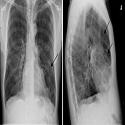

Aspect clinico-électrocardiographique d'embolie pulmonaire masquant une dissection aortique révélé par l'angioscanner thoracique

Daniella Rakotoniaina Masinarivo, Jenny Larissa Rakotomanana

PAMJ. 2017; 28: 3. Published 04 September 2017